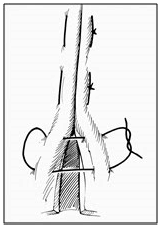

Nas suturas interrompidas os fios são fixados separadamente, podendo variar a tensão de acordo com a necessidade em cada ponto. É considerada mais segura, já que o rompimento de um ponto não inviabiliza a sutura toda. É menos isquemiante, confere maior permeabilidade à ferida e consegue força tensil maior e de modo mais rápido. Como desvantagens, possui uma elaboração mais lenta e trabalhosa. Relacione os tipos de sutura com as imagens e assinale a alternativa que apresenta a ordem correta.

1. Sutura em Jaquetão.

2. Sutura em “X” ou Sultan.

3. Sutura de Mayo.

4. Sutura de Halsted.